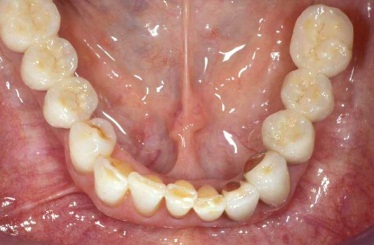

Náhrada jednoho zubu

Klasickým příkladem a indikací pro použití implantátu je ztráta jednoho zubu (v tomto případě v předním – frontálním úseku) v jinak zdravém, nepoškozeném chrupu.

Nejčastější příčinou takové ztráty je sportovní nebo dopravní úraz.

Náhrada jednoho zubu pomocí implantátu je možná také v postranním úseku chrupu. Při ztrátě většího počtu zubů ve frontálním nebo postranním úseku může být mezer uzavřena větším počtem jednotlivých implantátů.

Při ošetření pomocí jednotlivých implantátů zůstávají sousední zuby neporušené – intaktní. Při klasickém ošetření pomocí můstků musejí být tyto zuby obroušeny!